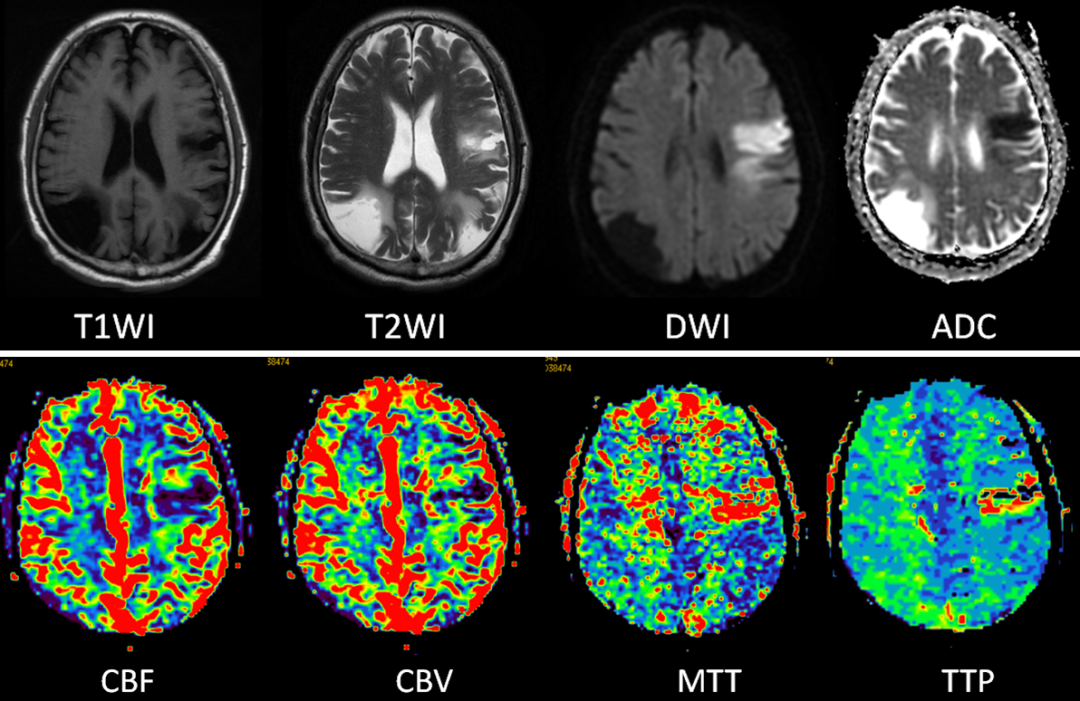

近期,影像诊断中心通过新开展磁共振脑灌注成像(PWI)技术,陆续为十多例脑疾患者进行检查,效果十分显著。据悉,与普通的磁共振检查相比,PWI技术能更加清晰准确显示疾患所在,为下一步治疗提供具体参数。

PWI即磁共振灌注成像,是一种反映组织微血管分布和血流灌注情况的MRI功能成像技术,具有较高的时间分辨率(小于2s即可包括全脑)和空间分辨率,操作简单,无放射性,可以在短时间内重复进行,具有良好的临床应用前景。

目前我院开展的PWI主要通过静脉团注对比剂使局部毛细血管内磁敏感性增加致局部磁场不均匀,质子自旋去相位,引起T2、 T2*或T1值的明显缩短,获得一系列动态影像,通过定量指标反映局部灌注情况。PWI在脑缺血性疾病的诊断中有非常重要的意义,联合多种MRI成像技术诊断效能更高、更准确,可以为临床制定治疗方案提供很多重要的信息。

多种MRI成像技术联合诊断更准确。